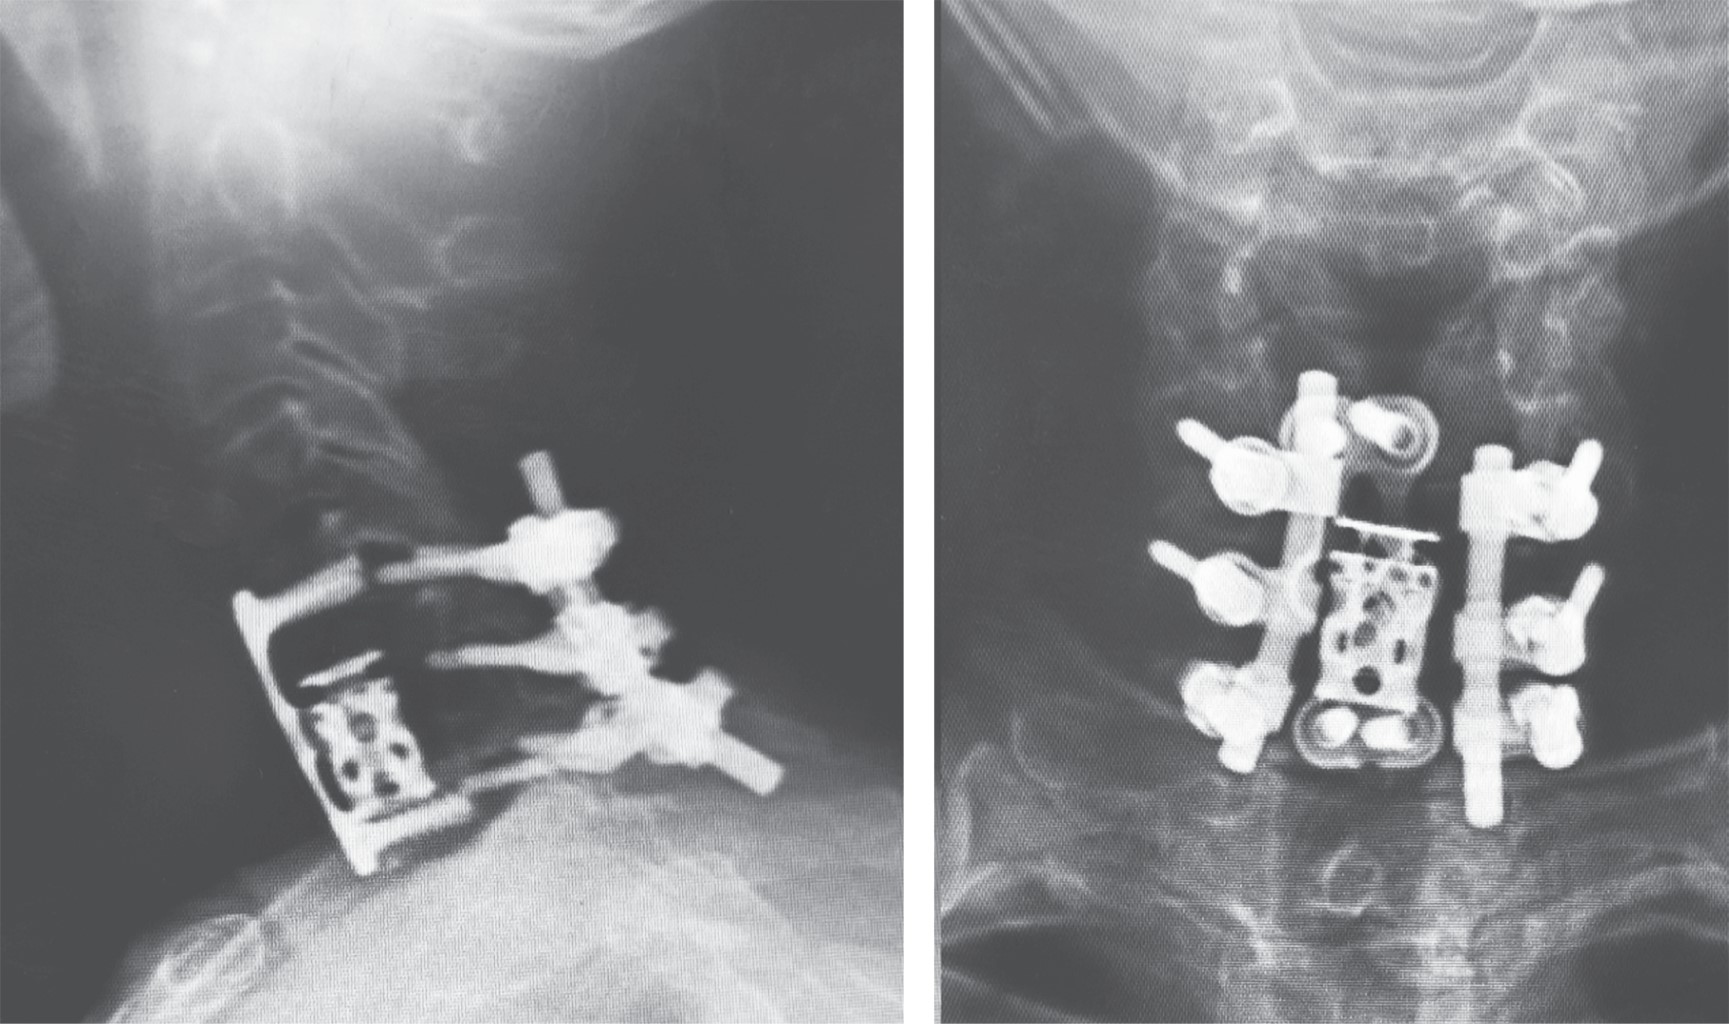

Subaxial cervical spine luxation is a frequent entity in polytraumatized patients, regularly accompanied by neurological injuries such as paraplegia or quadriplegia, requiring urgent surgical treatment in order to stabilize, align and decompress the nerve structures, sometimes it is not possible to perform this type of procedure early due to the general conditions of the patient or the conditions of the hospital units, leading to a late treatment, however, undiagnosed luxation occur, or in the worst case scenario, an inadequately treated injury with poor results that lead to an unsatisfactory evolution of the patient, with chronic pain and neurological deficit. We analyze the case of a patient with subaxial cervical spine luxation, with torpid evolution, requiring a new intervention two years after her injury, performed in three specific sequential times, achieving the patient's recovery and motor functionality.REFERENCES